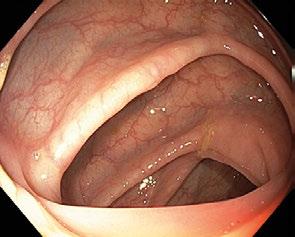

Obr. 1.5 Descendens s oválným až trojúhelníkovým lumen

Sestupný tračník (descendens, colon descendens ) sestupuje od slezinného ohbí (lineální flexura, flexura coli sinistra, flexura lienalis) kaudálně při levém okraji dutiny břišní a má délku 22–30 cm. Je užší než orální části tračníku a aborálním směrem se ještě zu-

žuje. Descendens ve většině případů nemá peritoneální závěs a je široce přirostlé se zadní stěnou břišní (tzv. sekundárně retroperitoneální orgán) (obr. 1.5) Slezinné ohbí je ostřejší a kraniálněji uložené než ohbí jaterní, je v kontaktu se slezinou a levou ledvinou a fixováno k bránici pomocí ligamentum phrenicolicum (obr. 1.6).